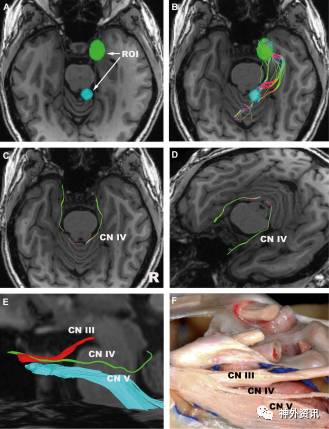

图5. 滑车神经。A.ROI分别置于滑车神经相邻的下丘和海绵窦;B.分割前的滑车神经(轴向位);C.分割后的滑车神经(轴向位);D.分割后的滑车神经(斜位);E.动眼神经、滑车神经和三叉神经(特写图和侧位),可观察到动眼神经和滑车神经在海绵窦内交叉;F.对应E图的解剖图。